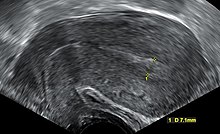

Transvaginal ultrasonography after an episode of heavy bleeding in an intrauterine pregnancy that had been confirmed by a previous ultrasononography. There is some widening between the uterine walls, but no sign of any gestational sac, thus in this case being diagnostic of a complete miscarriage.

A complete miscarriage is when all products of conception have been expelled; these may include the trophoblast, chorionic villi, gestational sac, yolk sac, and fetal pole (embryo); or later in pregnancy the fetus, umbilical cord, placenta, amniotic fluid, and amniotic membrane. The presence of a pregnancy test that is still positive as well as an empty uterus upon transvaginal ultrasonography does, however, fulfill the definition of pregnancy of unknown location. Therefore, there may be a need for follow-up pregnancy tests to ensure that there is no remaining pregnancy, including an ectopic pregnancy.[citation needed]